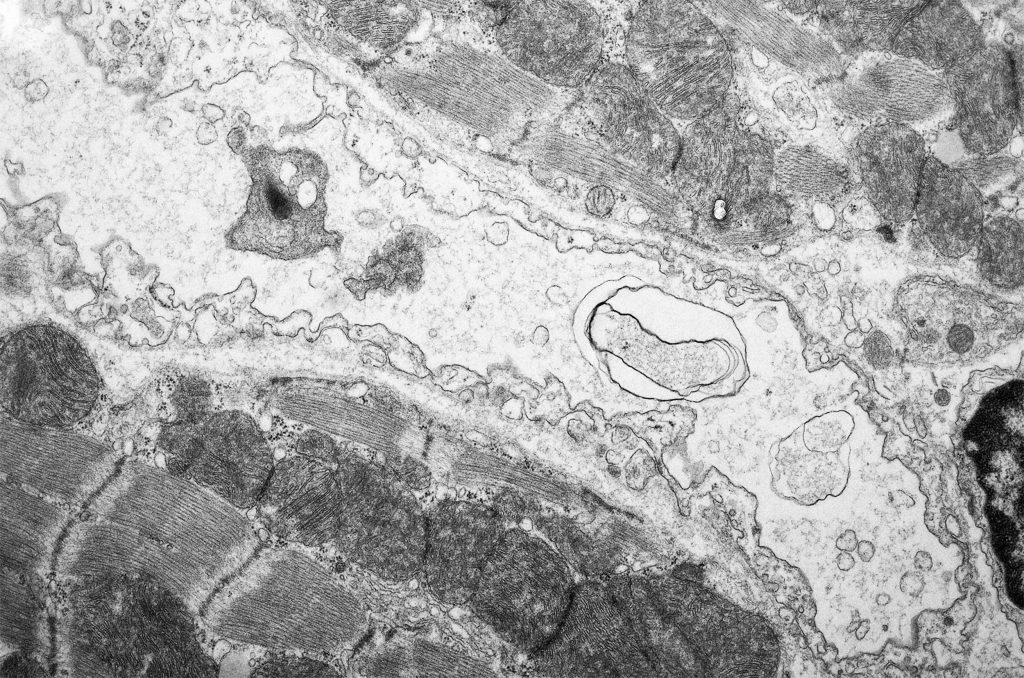

Elektromikroskooppikuva vaurioituneista endoteelisoluista doksorubisiinilla hoidetun hiiren sydämessä. (Kuva: Ilkka Miinalainen)

PNAS-tiedelehdessä julkaistu suomalaistutkimus paljasti, että doksorubisiini johti sydämen painon laskuun sekä pienten verisuonten vaurioitumiseen ja katoon hiirten sydämissä. Tutkimus osoitti kuitenkin myös, että tämä prosessi voitiin estää geeniterapialla, jossa käytettiin verisuonten kasvutekijää nimeltä VEGF-B. VEGF-B-kasvutekijä edistää verisuonten sisäpintaa verhoavien endoteelisolujen kasvua.

Tutkimustulokset osoittavat, että sydämen verisuonten sisäpinnan solukolla, endoteelilla, on oleellinen rooli sydämen suojaamisessa solunsalpaajien haittavaikutuksilta. – Havaintoon perustuvan geeniterapian ottaminen käyttöön potilaiden hoidossa vaatii kuitenkin vielä jatkotutkimuksia, Räsänen huomauttaa.